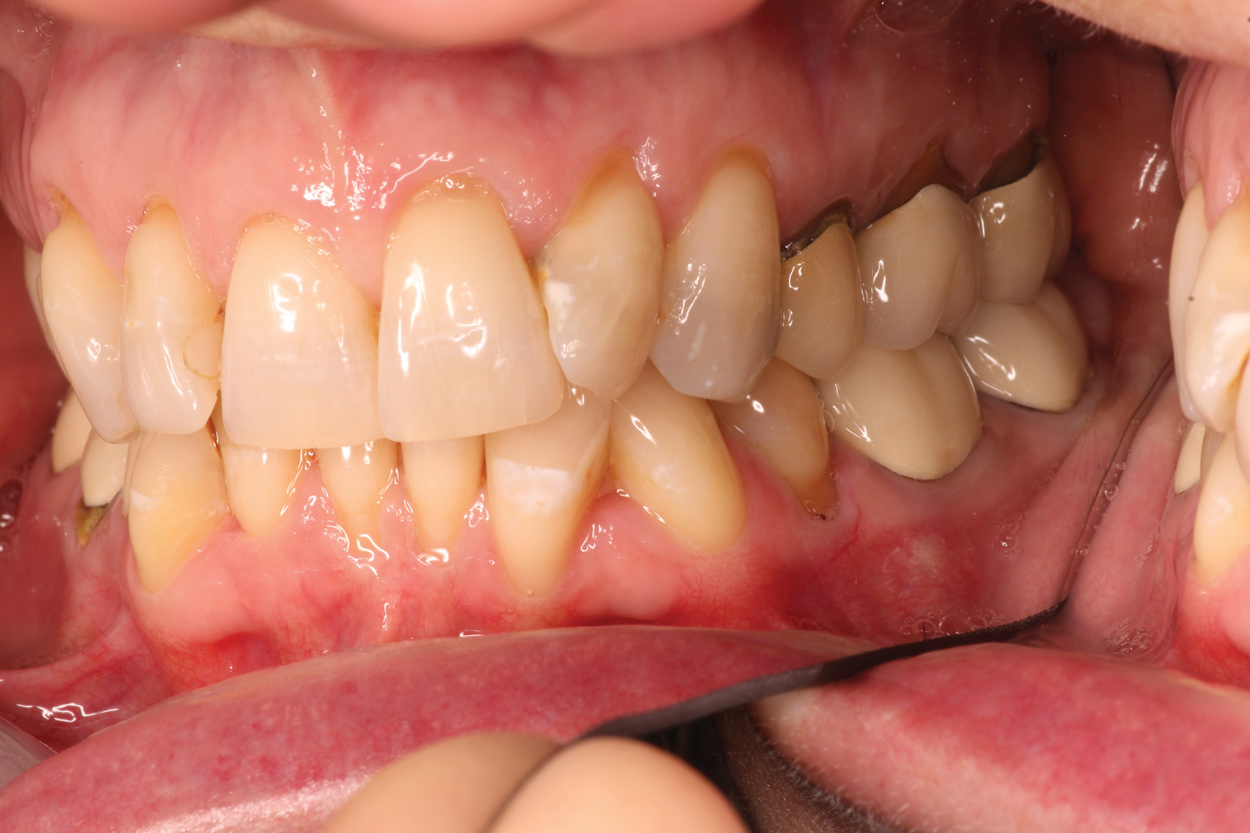

In another case, a 57-year-old patient presented with sensitivity for 6 months on tooth No. 18 which was increasing (Figure 3 and Figure 4). The clinician adjusted it to determine there was no occlusal component compounding the sensitivity. However the patient continued to experience sensitivity. To provide the patient relief, two applications of SDF were recommended. After the first application, which required only 10 minutes, the patient experienced a considerable decrease in sensitivity. A follow-up application of SDF two weeks later resulted in an additional charge for the placement of SDF, which added to the production of the appointment. The patient left with resolution of her complaint.

(3.) Patient presented with sensitivity for 6 months on tooth No. 18.

Figure 3

(4.) Patient presented with sensitivity for 6 months on tooth No. 18.

Figure 4